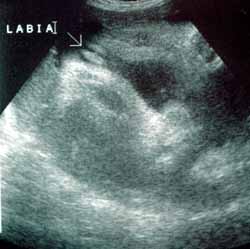

ثانيا : الولد

في الاسبوع ال19